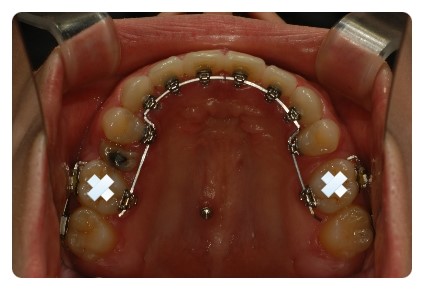

상하악 발치상태나 공간이 다름에도 불구하고

중심선이 크게 어긋나지않게 맞춰가면서 천천히 진행중이에요

거의 다 닫혀가는 상악 !!

입천장 와이어랑 고무줄도 떼엇어요